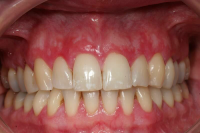

Parodontal stabilitet karakteriseras av framgångsrik behandling genom kontroll av lokala och systemiska riskfaktorer, vilket resulterat i

• minimal blödning vid sondering (BVS < 10 % av tandytorna)

• fickdjup < 3 mm

• ingen progressiv parodontal nedbrytning/vävnadsförlust

• optimal förbättring i övriga kliniska parametrar hos behandlad parodontitpatient.